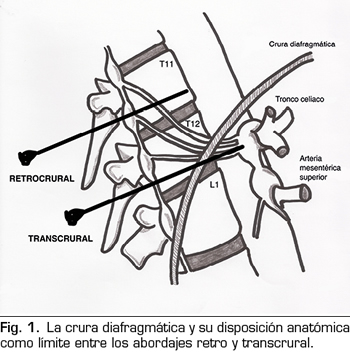

La crura diafragmática va a determinar anatómicamente si el bloqueo realizado representa un verdadero bloqueo del plexo celiaco o se trata de un bloqueo de los nervios esplácnicos (Figura 1). Si la punta de la aguja queda posterior a la crura, los nervios bloqueados serán los esplácnicos. Las agujas dispuestas a nivel del cuerpo vertebral de T11 siempre quedarán por detrás de la crura. Por debajo de este nivel, la crura se hace posterior y se inserta en los cuerpos vertebrales de T12 y L1. A esta altura, las agujas pueden ser colocadas tanto anteriores como posteriores a la crura. El abordaje clásico de Kappis (12) de posicionamiento de la aguja en el borde anterior del cuerpo vertebral suele resultar en un bloqueo retrocrural, demostrado en trabajos posteriores en cadáveres con TAC (13). Para conseguir un verdadero bloqueo anterior a la crura, se debe avanzar más la aguja para que quede anterior a la aorta abdominal.

Aclarada esta cuestión, podemos clasificar los abordajes percutáneos de la siguiente manera (Figura 2):